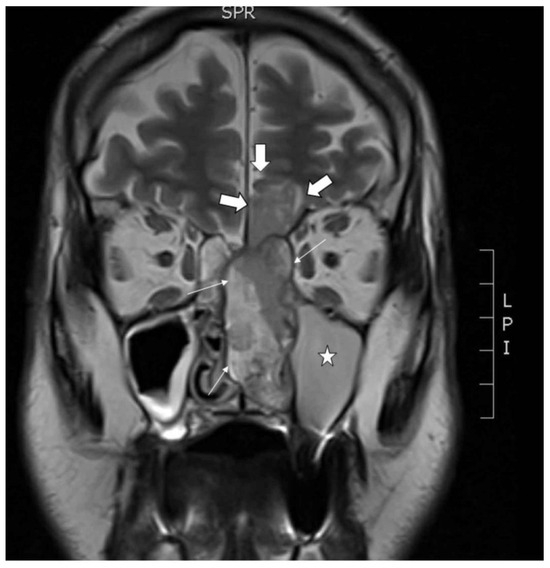

A primary tumor sample and peripheral blood were obtained from a 68 year old male patient who presented with nose bleeding and fever episodes. He was a habitual smoker and occasional drinker, but had no history of exposure to wood, leather or textile dust, or industrial chemical substances as glues, formaldehyde, chrome or nickel. He had been previously treated with xazal and rinobanedif without any benefit. Rhinoscopy showed an irregular large 7 × 4 × 2 cm bleeding tumor occupying the whole left nasal cavity invading 2 × 2 cm into the brain through the cribriform plate (Figure 1). There were no lymph node or distant metastases nor changes in the oropharynx. The tumor was surgically resected but no free margins could be warranted. Adjuvant radiotherapy ended six months after surgery, at which point an MRI scan revealed a large intracranial progression and local recurrence. The patient died a short time later. This study was performed in accordance with the approved guidelines of the Ethics Committee of the Hospital Universitario Central de Asturias, and informed consent was obtained from the patient.

Figure 1.

Coronal MRI showing the tumor in the left nasal cavity with a nasal component (thin arrows) and an intracranial component (thick arrows) in the shape of an hourglass. Asterisk in the maxillary sinus filled with mucus retention.